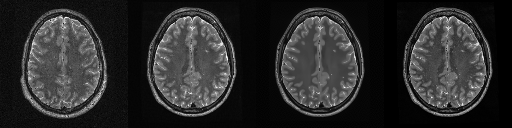

HCP T2w dataset

We utilize images from the publicly available Human Connectome Project (HCP) [51] T2-weighted (T2w) images dataset for the task of compressed sensing, which contains brain images from 47 patients. The HCP dataset includes cross-sectional images of the brain taken at different levels and angles.

Compressed sensing

We train a flow-based model from scratch on 10,000 randomly sampled images, utilizing the ncsnpp architecture [9] with minor adaptations for grayscale images. We employ compression rates , meaning . The measurement operator is given by a subsampled Fourier matrix, whose sign patterns are randomly selected. We evaluate our reconstruction algorithm’s performance on 200 randomly sampled test images.

We present the quantitative and qualitative results of compressed sensing in Tab. 1 and Fig. 4, respectively. As shown in Tab. 1, our method consistently achieves the best performance across varying compression rates . In Fig. 4, our method produces reconstructions that are more faithful to the original images, with fewer artifacts, leading to higher accuracy and clearer details.